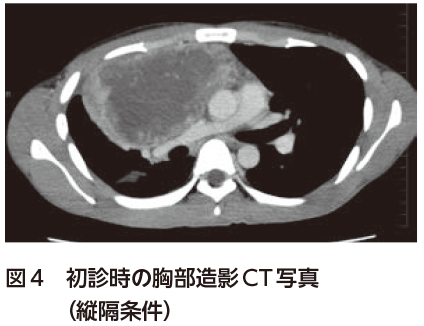

解答 解説 微熱 倦怠感 吸気時の胸痛を主訴に受診した歳代男性 実践 画像診断q A 羊土社 レジデントノート 羊土社